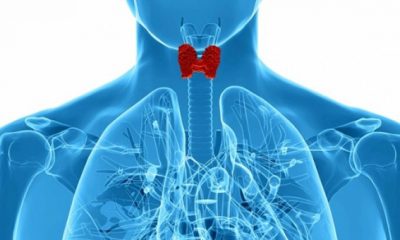

Πως να ξαναρυθμίσετε το θυροειδή σας, να κάψετε λίπος και να ενεργοποιήσετε το μεταβολισμό σας;

14 Φεβρουαρίου 2019Μια υπολειτουργεία στη κατάσταση του θυροειδούς παρουσιάζεται όταν ο θυρεοειδής αδένας δεν παράγει επαρκείς ποσότητες θυρεοειδικών...

Πώς θα καταλάβετε ότι έχει πρόβλημα ο θυρεοειδής σας

13 Φεβρουαρίου 2019Ο θυρεοειδής σας είναι ένας αδένας σε σχήμα πεταλούδας στον λαιμό σας, ακριβώς πάνω από την...